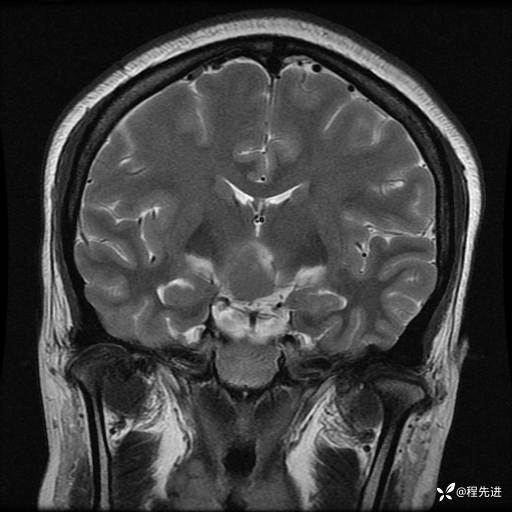

MRI平扫+增强:

T2: